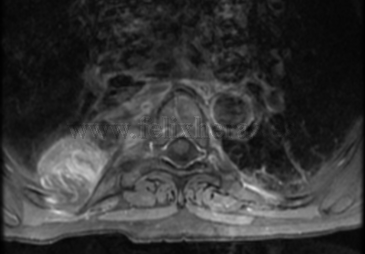

Tumor de mediastino posterior

Neuroma